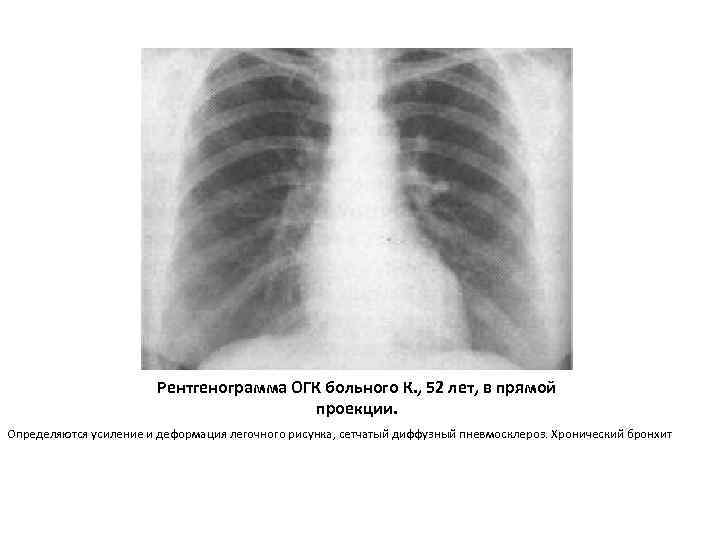

Ячеистая деформация легочного рисунка: медицинская визуализация